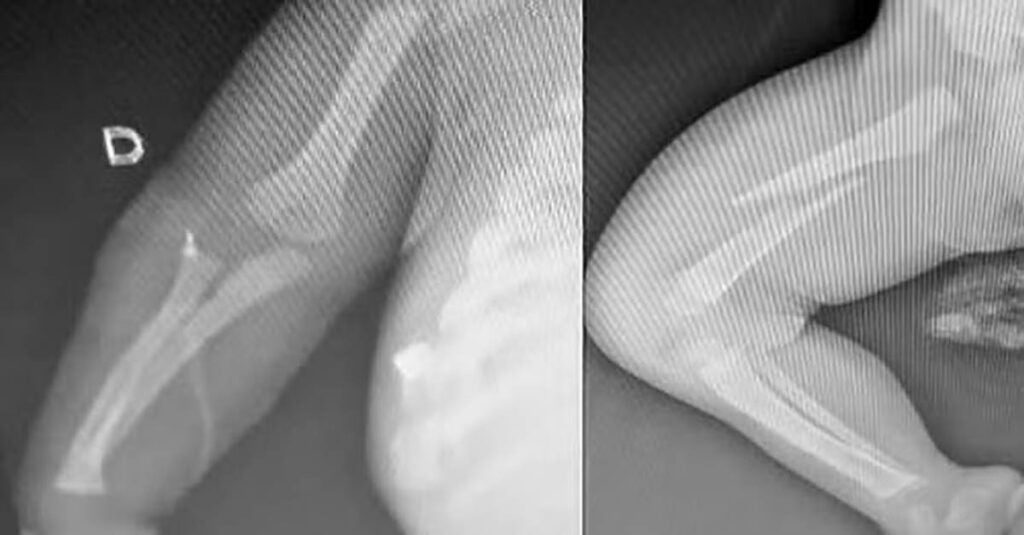

A criança apresentava fraturas nos braços, fêmur e costela, além de perfuração pulmonar e diversos hematomas pelo corpo. O bebê chegou desmaiado ao hospital, e o pai, de 30 anos, disse que a queda teria ocorrido enquanto o bebê dormia sobre sua barriga.